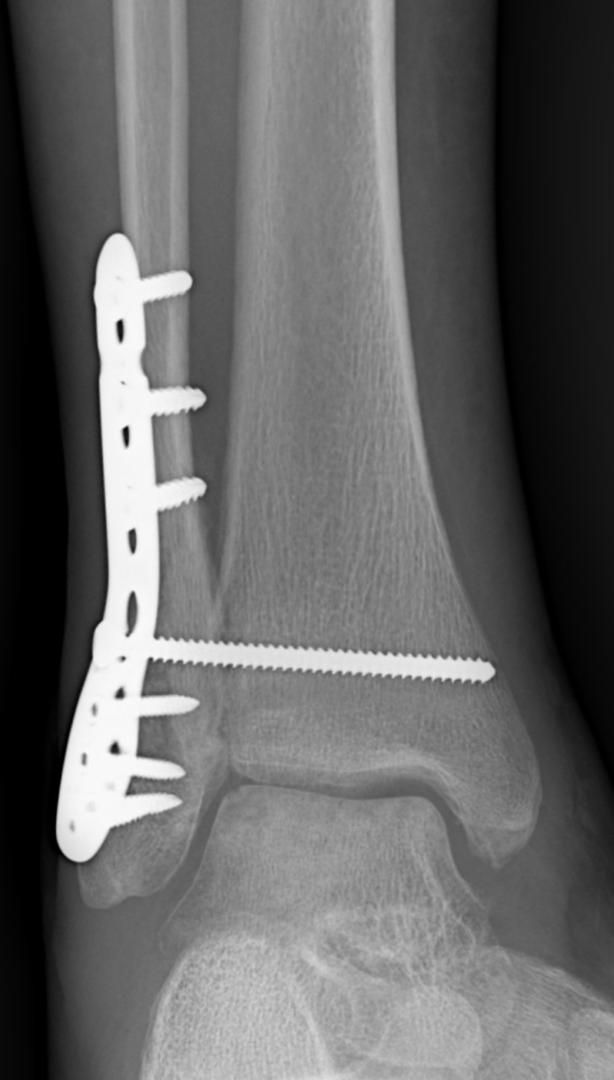

General & Complex Trauma